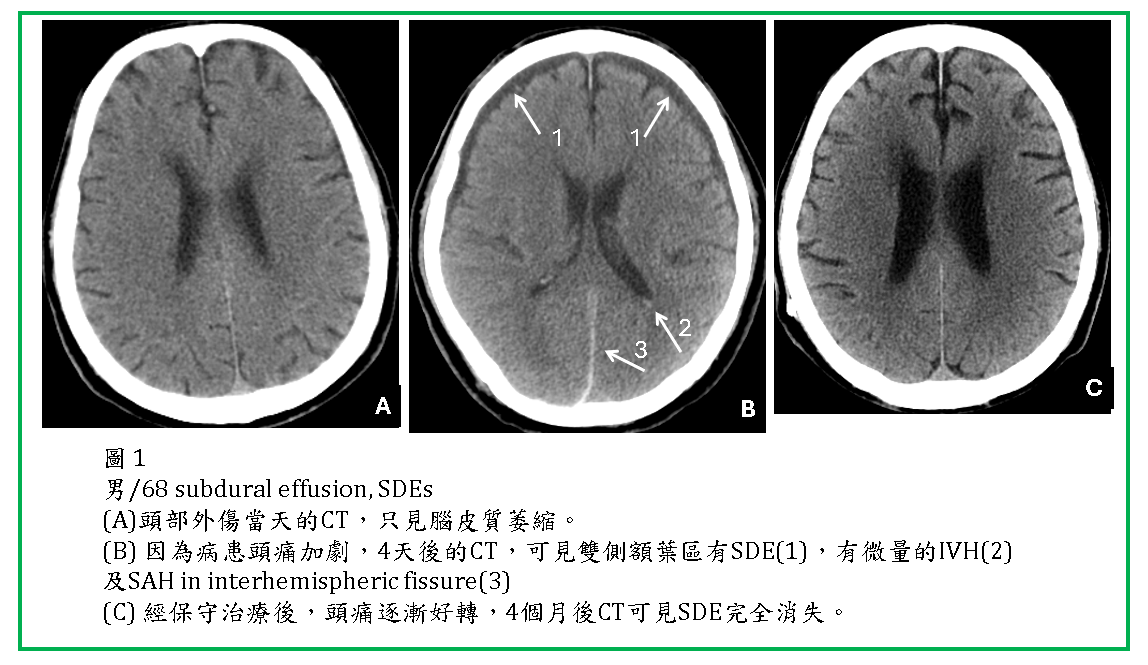

外傷後數天SDE才逐漸形成,而且通常都是雙側性的(圖1,2,3) 。有些是急性subdural hematoma沒處理,血塊逐漸演變成subdural effusion.

SDE通常位於大腦額頂葉外(圖1,2,3,4) ,有時也會在後顱窩,小腦天幕(tentorium)邊,及大腦鐮(falx)邊(圖3)。

多數SDEs會自行吸收掉,不需外科引流。